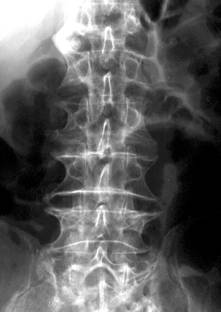

Modificarile radiologice ale spondilodiscitei tuberculoase sunt:

foarte mici focare osteolitice in apropierea discului, adesea invizibile radiografic;

diminuarea inaltimii spatiului discal ce antreneaza modificari de ax ale coloanei vertebrale (cifoza sau scoliaza);

stergerea suprafetelor discale si structura neomogena a corpurilor vertebrale adiacente discului, cu zone de osteoliza imprecis delimitate; localizarea leziunilor distructive fata-n fata pe cele doua platouri vertebrale implicate realizeaza asa zisa imagine “in oglinda”;

deformarea si reducerea, uneori extrema, a inaltimii corpilor vertebrali cu modificari de ax ale coloanei (cifoza pottica), dislocari, luxatii;

abcesul rece (pottic) apare ca o opacitate uni sau bilaterala ce proemina lateral, omogena, bine delimitata, depasind apofizele transverse. Abcesele din regiunea toracala medie nu migreaza la distanta si stagneaza in spatiul costovertebral sau intercostal, putand eroda coastele. Abcesele toracolombare coboara uneori pe teaca psoasilor in regiunea lombara, astfel ca vor modifica (bomba) umbra psoasului. Abcesele din regiunea cervicala deplaseaza anterior traheea si esofagul;

modificari reconstructive sub forma liniilor de demarcatie, zone de ingrosare a structurii osoase ce delimiteaza leziunea si fac sa reapara conturul vertebral care se recalcifica;

tardiv apar punti osoase intervertebrale ce demonstreaza fuziunea dintre vertebre;

evolutia fara tratament duce la distrugeri importante ale corpurilor vertebrale, aparitia sechestrelor si mari modificari de statica.